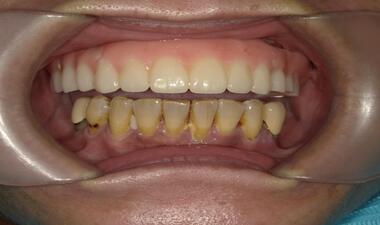

術後

裝戴固定

Full Arch 上顎假牙